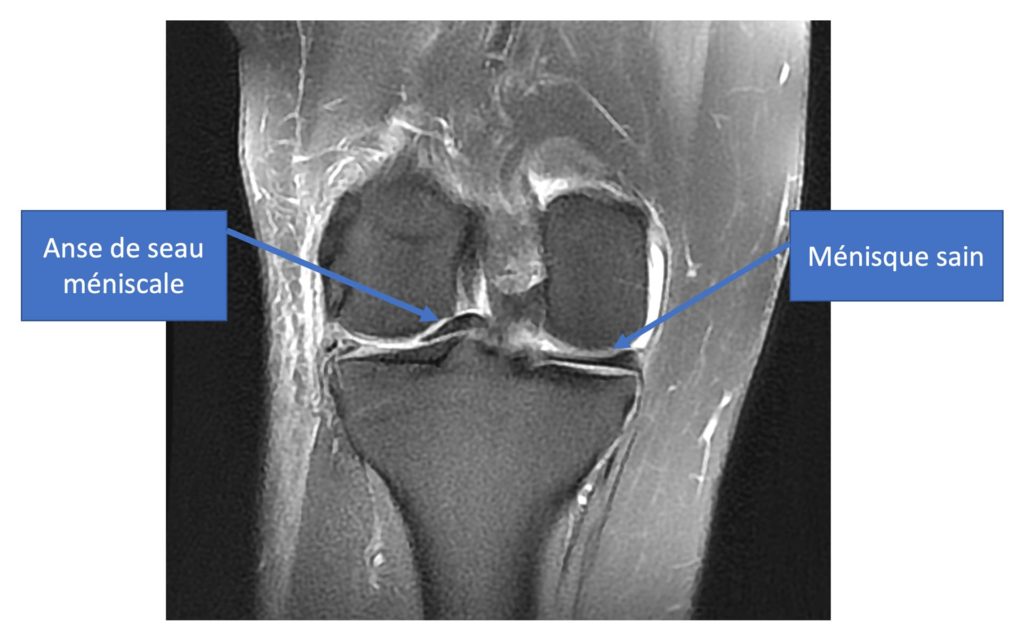

Chirurgie du Ménisque DR ANTOINE COMBES. Deux semaines après l opération j 'ai commencé les séances de kiné avec un total de 25 rendez vous. Ski: Réveille les douleurs si pratique intensive - j'en fait mais prudemment